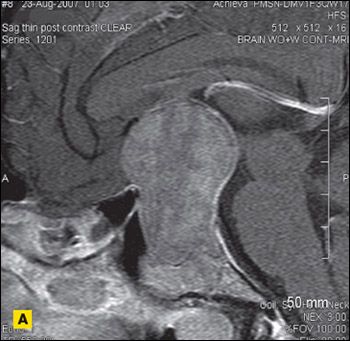

MRI scans of the brain revealed a 6 × 6 × 4-cm sellar mass with suprasellar and parasellar extension encasing the right cavernous sinus and carotid artery (Figure 2), which explained the vision loss.

Figure 2 – Sagittal (

A

), coronal (

B

), and axial (

C

) postcontrast MRI scans of the brain revealed a sellar mass of 6 × 6 × 4 cm with suprasellar and parasellar extension encasing the right cavernous sinus and carotid artery.